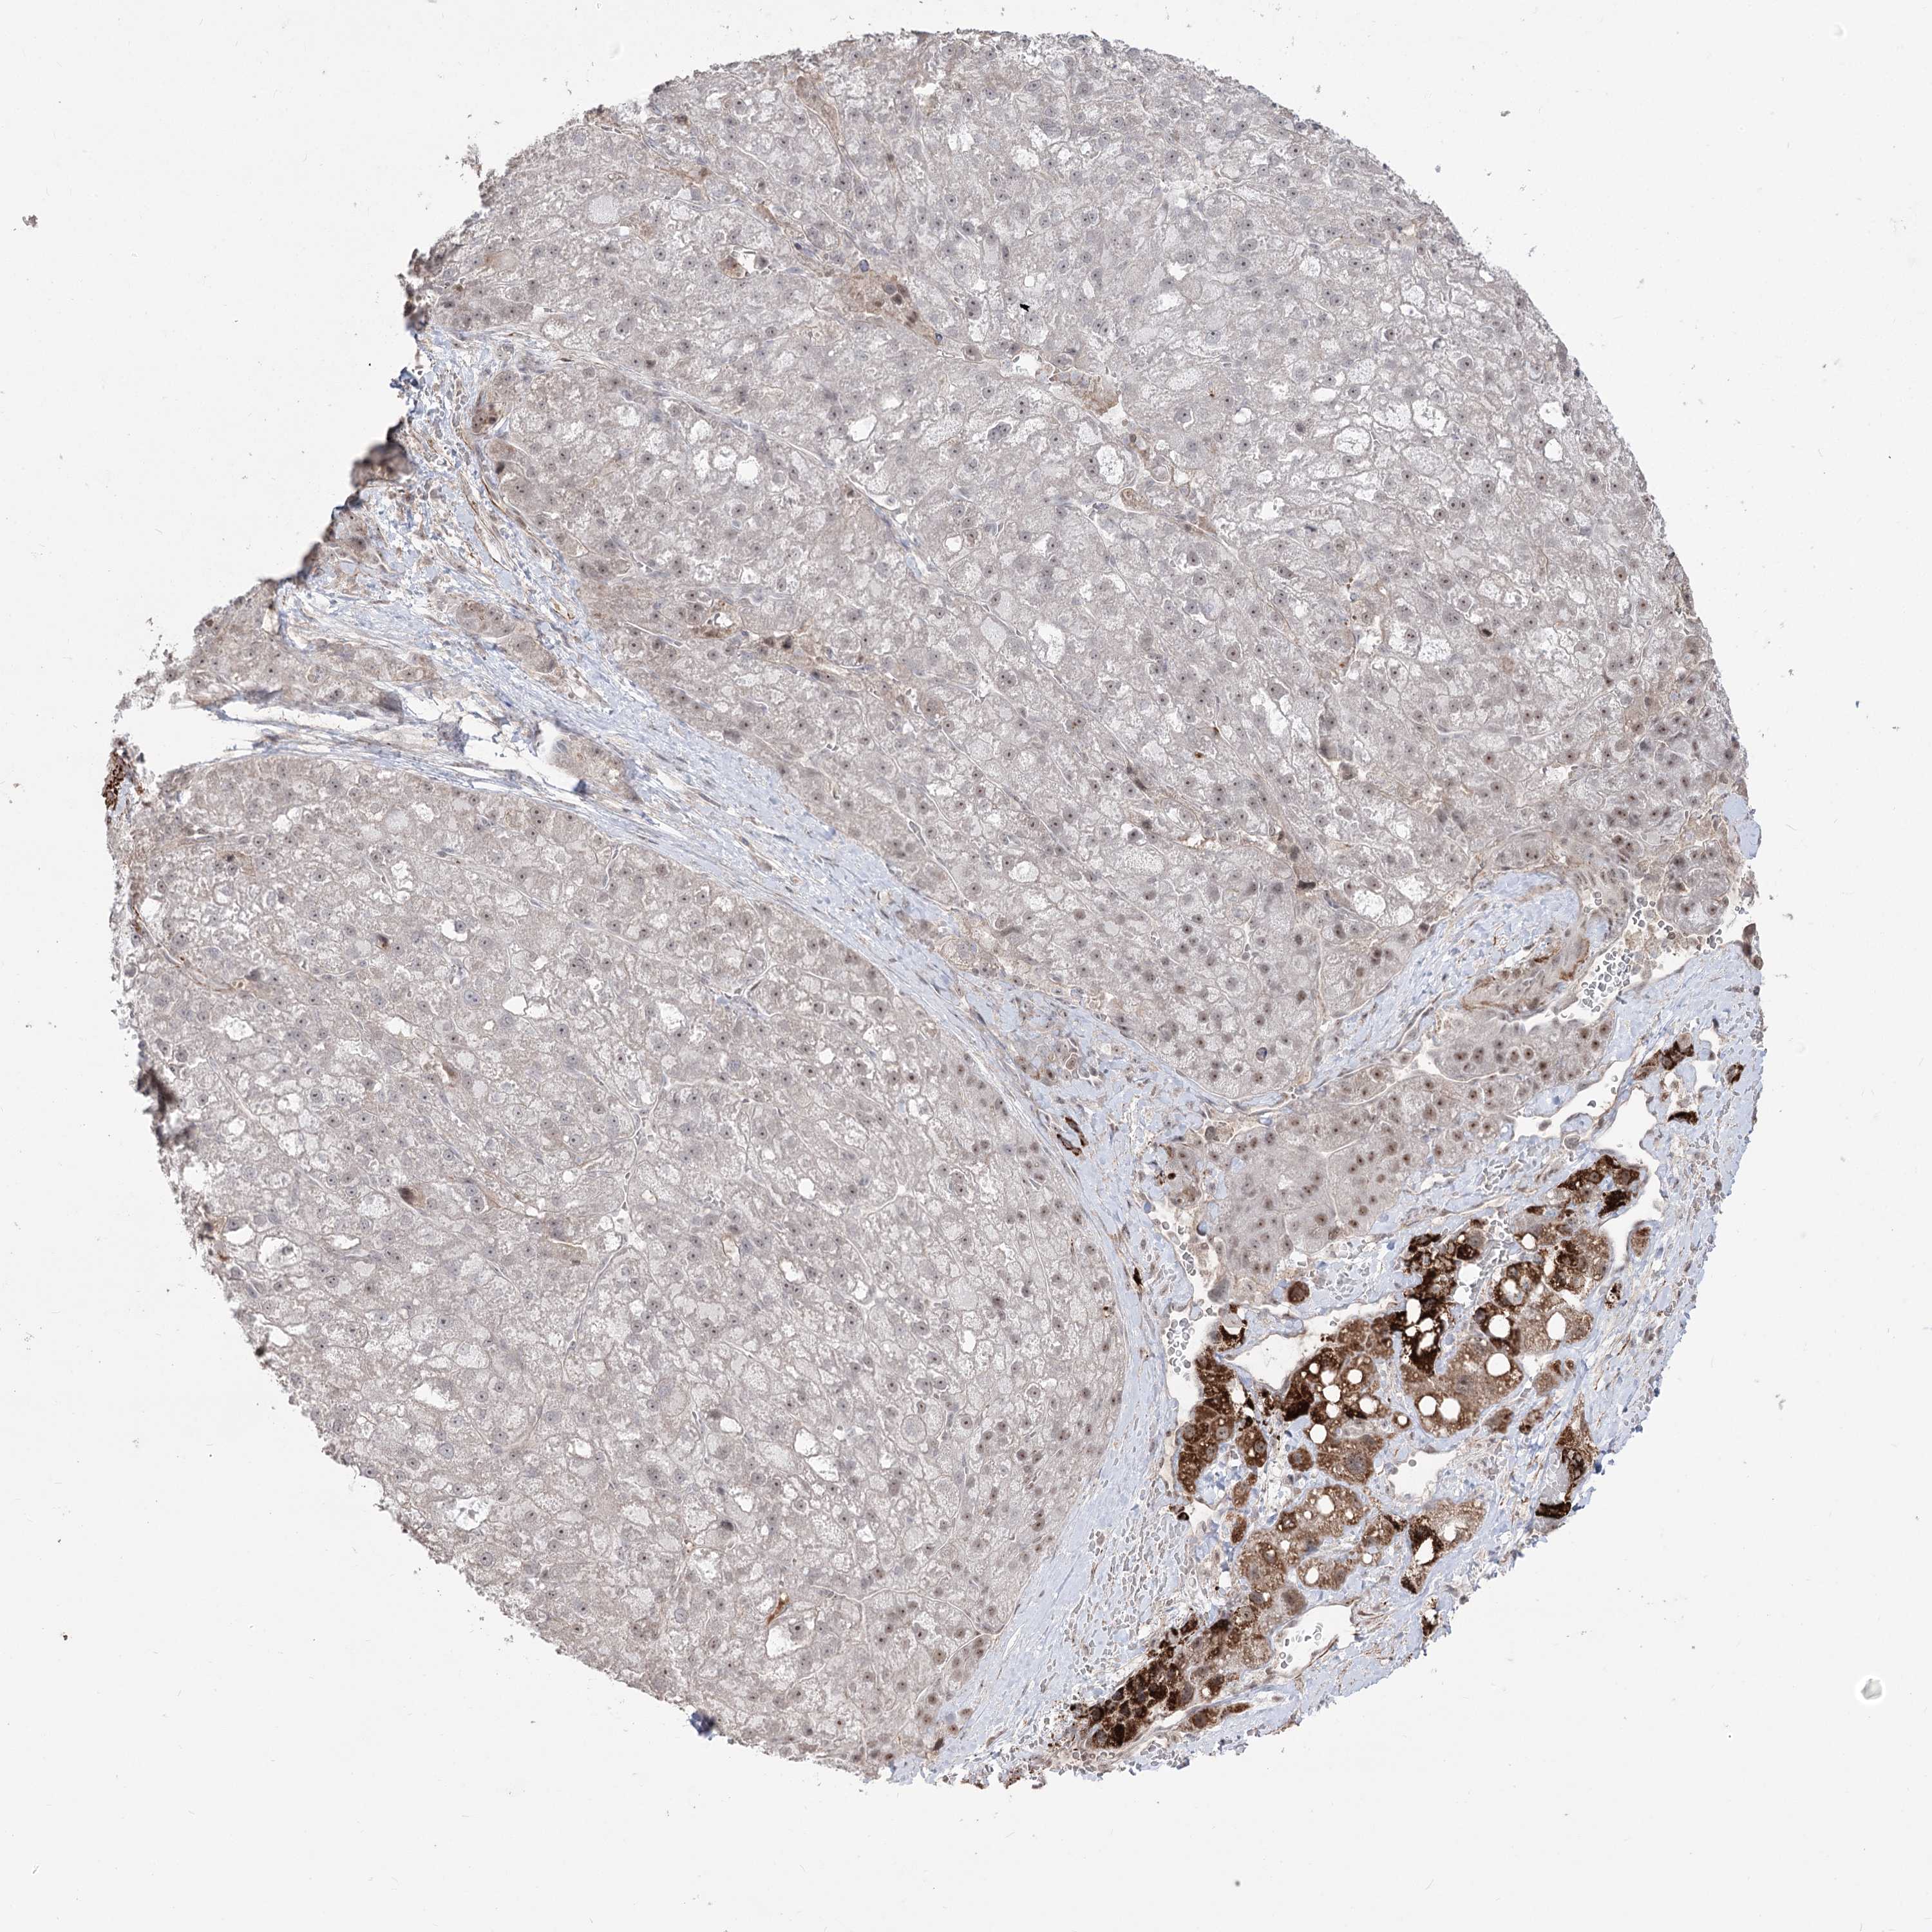

LIVER CANCER - Protein expressioni

A mouse-over function shows sample information and annotation data. Click on an image to view it in a full screen mode. Samples can be filtered based on level of antibody staining by selecting one or several of the following categories: high, medium, low and not detected. The assay and annotation is described here.

Note that samples used for immunohistochemistry by the Human Protein Atlas do not correspond to samples in the TCGA dataset.

Antibody stainingi

Antibody staining in the annotated cell types in the current human tissue is reported as not detected, low, medium, or high, based on conventional immunohistochemistry profiling in selected tissues. This score is based on the combination of the staining intensity and fraction of stained cells.

Each image is clickable and will lead to virtual microscopy that enables deeper exploration of all samples and also displays staining intensity scores, fraction scores and subcellular localization as well as patient and tissue information for each sample.

Antibody HPA035959

Antibody HPA035960

Staining

High

Medium

Low

Not detected

Intensity

Strong

Moderate

Weak

Negative

Quantity

>75%

75%-25%

<25%

None

Location

Nuclear

Cytoplasmic/membranous

Cytoplasmic/membranous,nuclear

Cholangiocarcinoma

Carcinoma, Hepatocellular, NOS